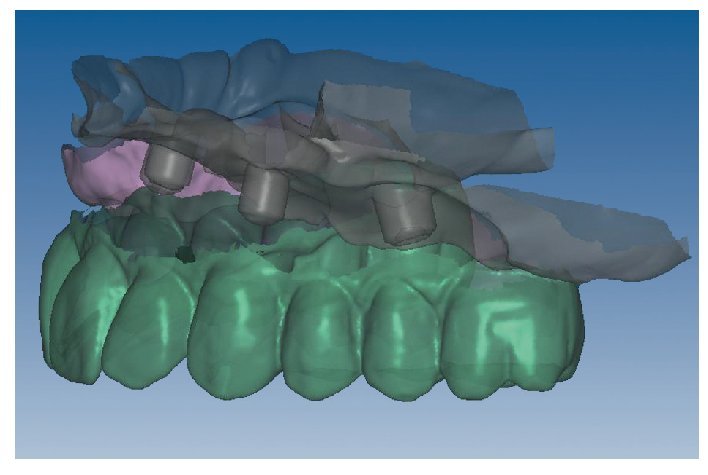

Mediante el uso de un escáner óptico de luz estructurada, los protocolos CAD registran los primeros datos relativos al modelo maestro con las correspondientes posiciones de implante (figs. 87 y 92). En el siguiente paso tiene lugar la digitalización de la planificación, previamente realizada en cera de escaneo matificada, de la restauración definitiva (figs. 88, 90 y 93). La subsiguiente conciliación de los datos mediante el uso del software de diseño dental permite al protésico planificar virtualmente el resto del procedimiento (figs. 89 y 91, 94 a 96) a partir del diseño de las estructuras (figs. 97 y 98).

Fig. 90. La posición de los implantes en relación con la planificación.

Figs. 94 a 95. Planificación CAD de la estructura del maxilar inferior, en representación lingual y vestibular.

Figs. 96 a 98. El diseño definitivo de la estructura del maxilar inferior, desde distintas perspectivas.